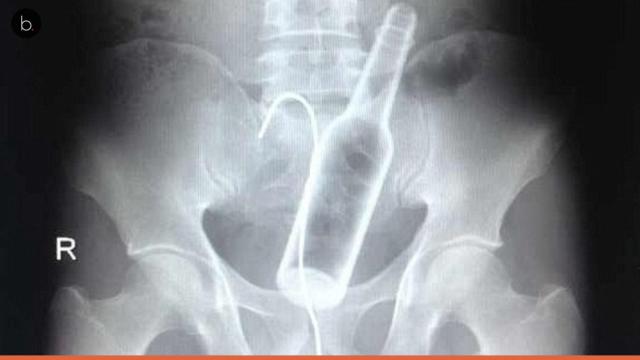

1 - Garrafa

Uma garrafa apareceu no corpo dessa pessoa, e está bem próxima da saída anal. Isso pode ter sido uma brincadeira sexual, pois os médicos relatam que muitas pessoas chegam aos hospitais com objetos estranhos usados durante a relação.